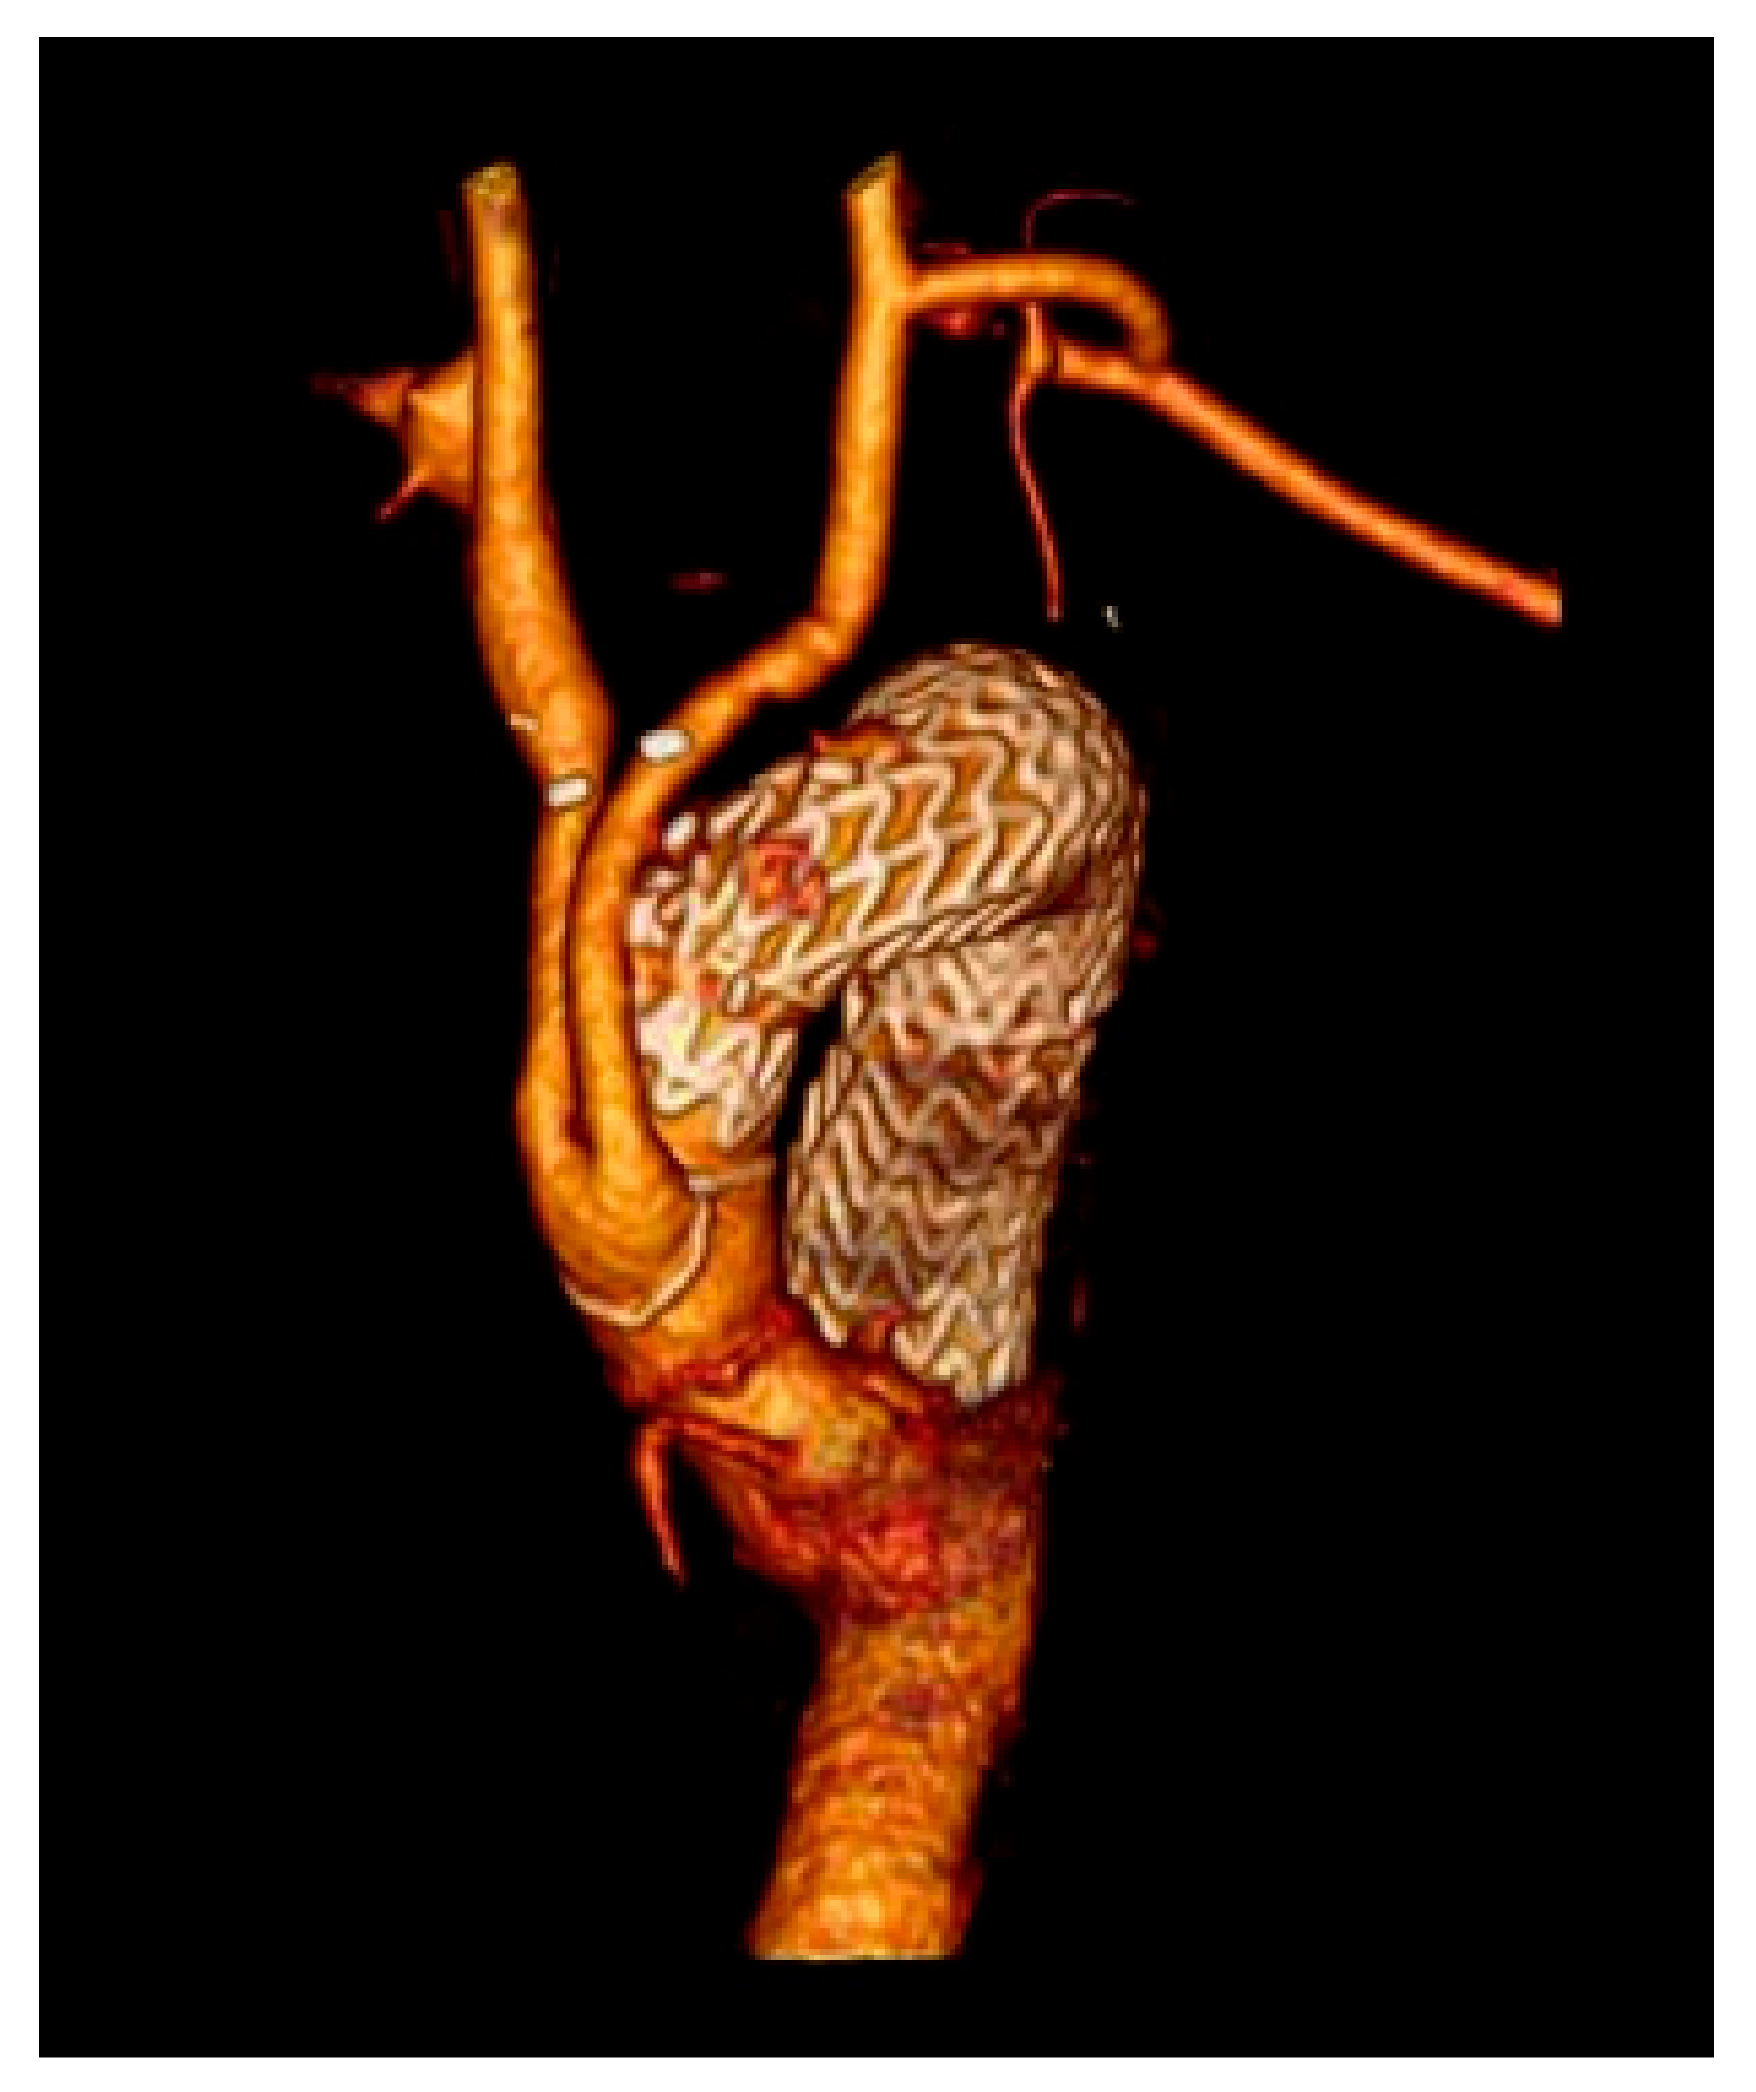

Technically, in 100% of the cases, the endovascular step succeeded. Follow-up was 100% complete with 0% type Ia endoleak rate (Figure 4).

Figure 4.

3 years follow-up type II debranching CT scan.